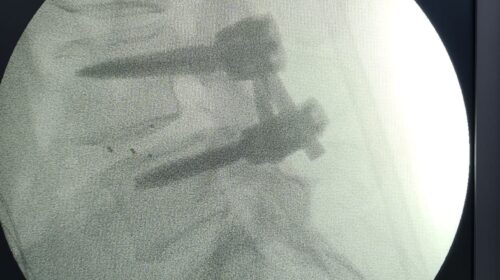

“Fueron tres tipos de exposiciones. Una de ellas es la cirugía en vivo, donde realizamos dos procedimientos en pabellón, acompañados por destacados especialistas, el Dr. Carlos Zanardi, presidente de la Sociedad de Neurocirugía de Buenos Aires, Argentina y el Dr. Cristiano Meneses, director del Instituto de Columna de Brasil”, precisó el Dr. Muñoz.

A continuación, compartimos las fotografías enviadas por el Dr. Avaria a la Sociedad de Neurocirugía de Chile: